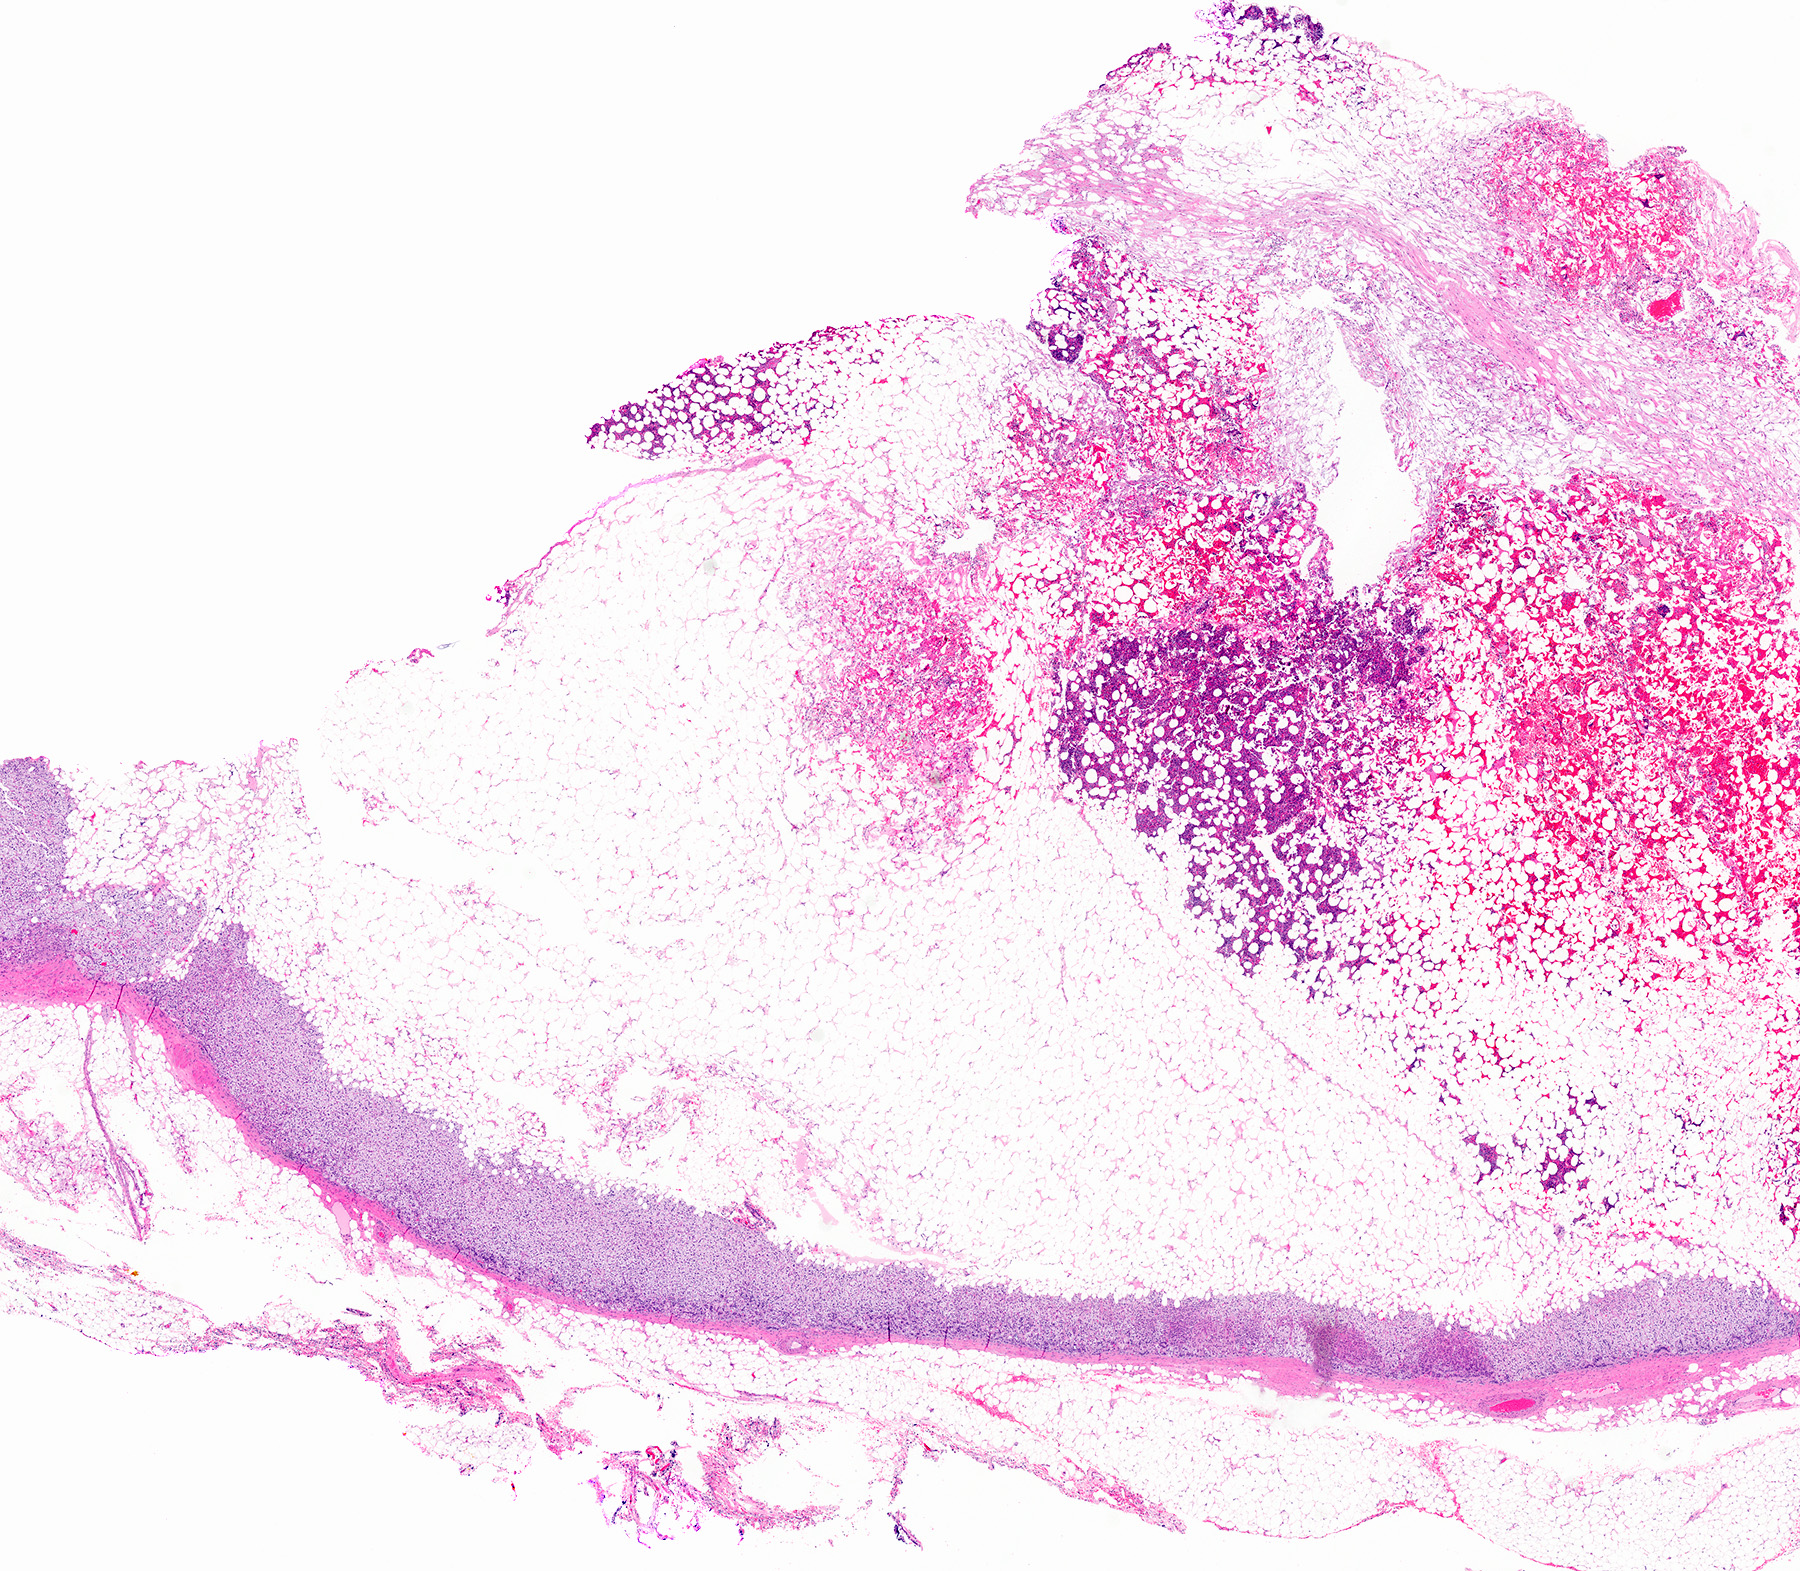

- Well demarcated, unencapsulated, yellow (mature fat) to red (hemorrhage) nodule depending on the composition; if large, hemorrhage and infarction are common

- Mean size is 10 cm (0.5 - 43 cm); weight may be up to 11 kg

Gross images

Contributed by Debra L. Zynger, M.D. and Anil Parwani, M.D., Ph.D.

Microscopic (histologic) images

Contributed by Debra L. Zynger, M.D., Anil Parwani, M.D., Ph.D., O. Hans Iwenofu, M.D., Ph.D. and @ThatGlassTho on Twitter